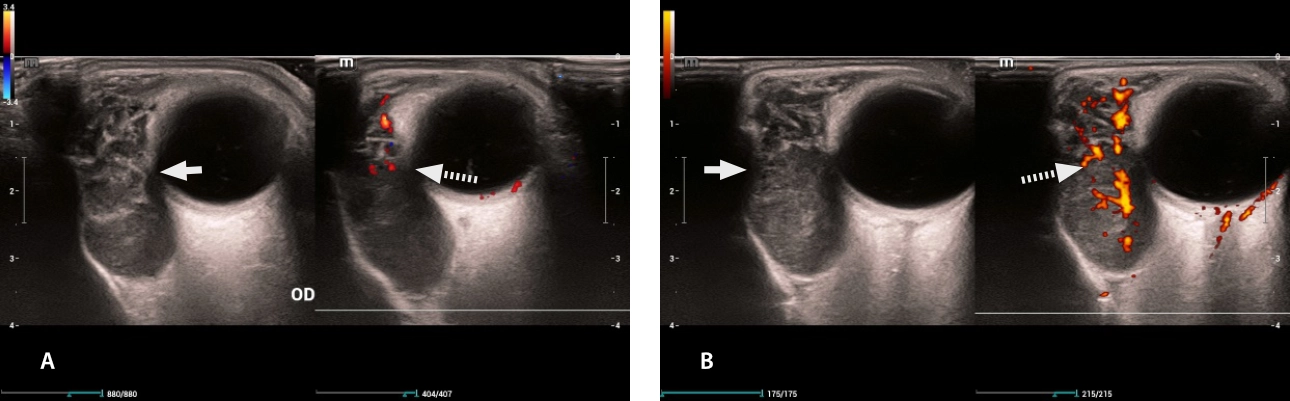

Fig. 4. Lacrimal glands: (A) right, (B) left. Both were presented with hypoechogenic images (white arrow), with vascularity preserved on color Doppler/Power Doppler (dashed arrow).

lymphoma-simulator-fig5-pc

Fig. 5 Multiple cervical lymphadenopathy: (A) Left laterocervical lymphadenopathy (B) Left submandibular lymphadenopathy: rounded morphology, with loss echogenic fat center on grayscale (white arrow), loss of vascular hilum on color Doppler (dashed arrow).

lymphoma-simulator-fig6-pc